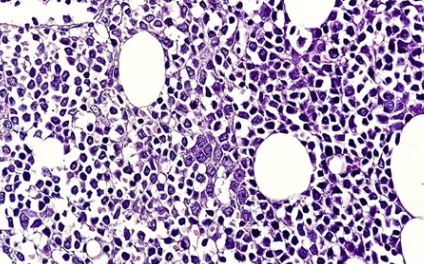

혈액암은 단순히 피에 생기는 암이 아니라, 혈액 세포가 만들어지는 과정에 이상이 생겨 암세포로 자라는 질환입니다. 크게 다음 세 가지로 나뉘어요.

| 다발성골수종 | 골수 내 형질세포가 비정상적으로 증식 |